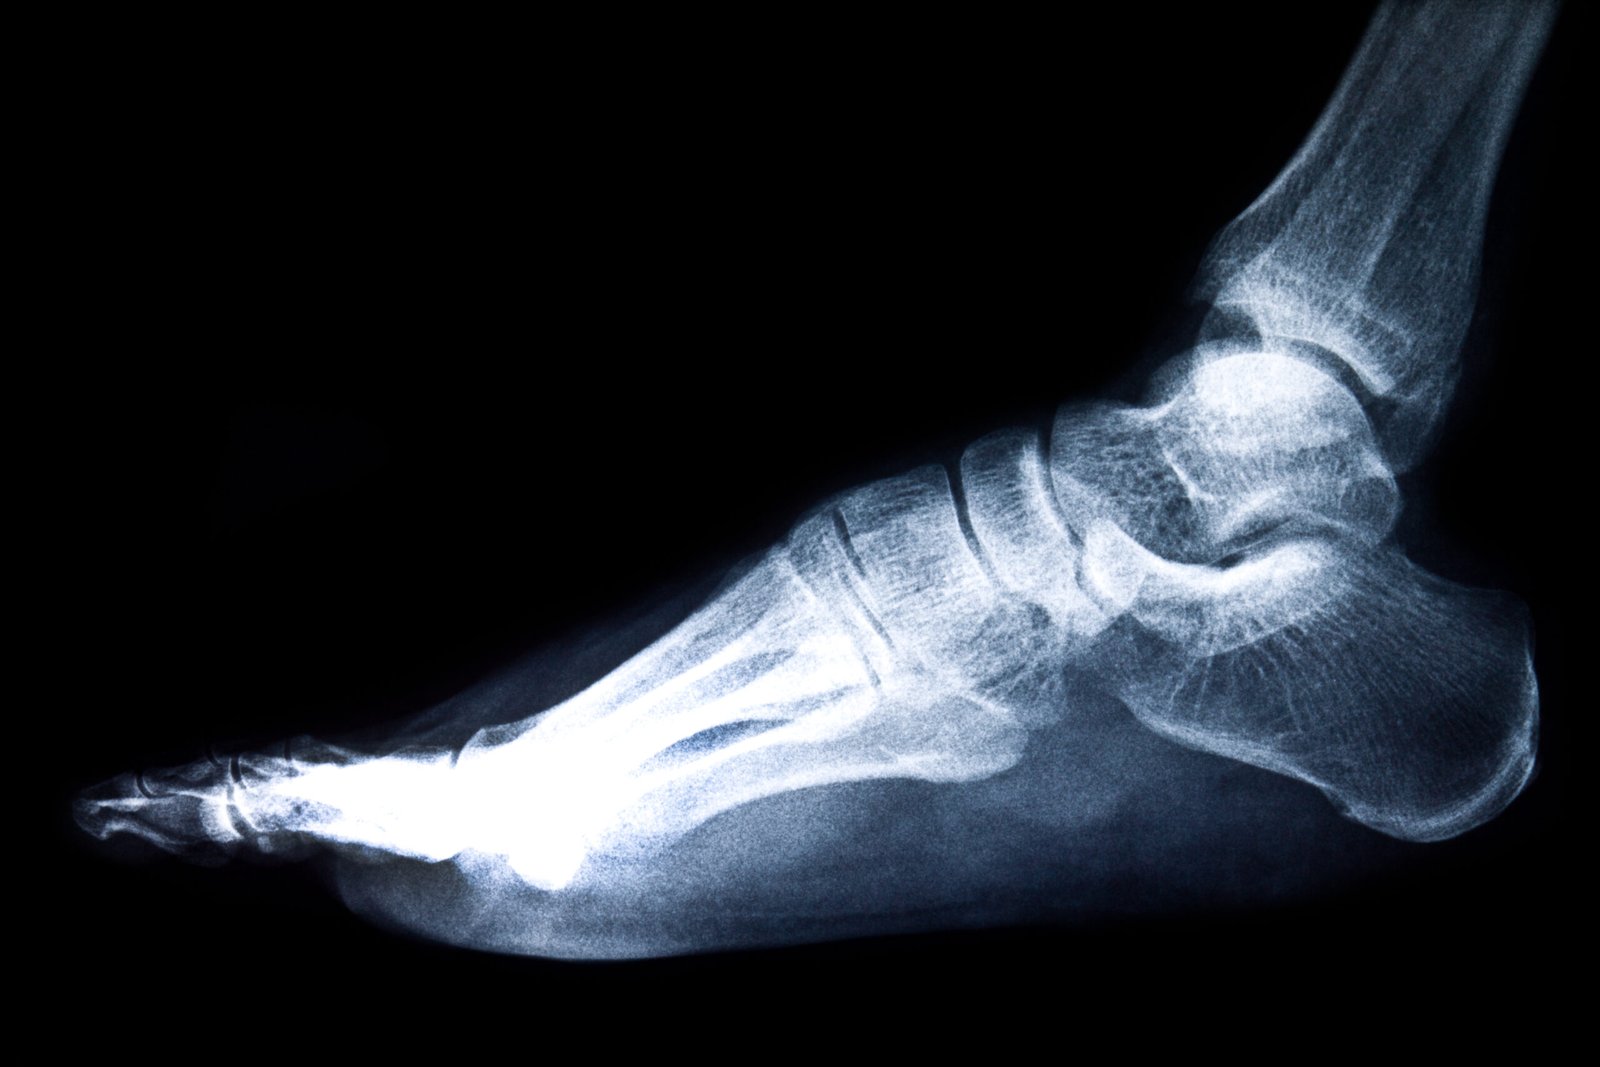

The foot and ankle region has 26 bones, 33 joints, and an abundance of ligaments and tendons. The important structures include the plantar fascia and the Achilles tendon, and the bursae. These elements integrate in joint support, locomotion, and balance. It can cause localized pain and impairment in functioning as a result of damage, overuse, or degeneration of any structure.

Diagnosis of Foot & Ankle Pain